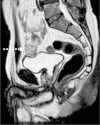

Case presentation: A 62-year-old patient previously diagnosed and treated due to pulmonary sarcoidosis has developed an omental metastatic lesion 13 years after having undergone open extraperitoneal partial nephrectomy for T1 clear-cell RCC. Constitutional symptoms and imaging findings that were attributed to the presence of a sarcomatoid paraneoplastic syndrome triggered by the development this metastatic focus complicated the diagnostic work-up. Biopsy of the [18F]-fluorodeoxyglucose (+) lesions confirmed the diagnosis of metastatic RCC and the patient was managed by the resection of the omental mass via near-total omentectomy followed by targeted therapy with a tyrosine kinase inhibitor.

Conclusion: To our knowledge, this is the first reported case of metachronously developed, isolated omental metastasis of an initially T1 clear-cell RCC. Constitutional symptoms, despite a long interval since nephrectomy, should raise the possibility of a paraneoplastic syndrome being associated with metastatic RCC. Morphological and molecular imaging studies together with histopathological documentation will be diagnostic.